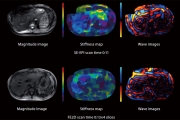

MR-elasztográfia (MRE)

Az MRE az egyetlen olyan MRI-technológia, amelyet validáltak a májfibrózis stádiumának megállapítására. Az MRE szerepét egyre inkább elismerik a multidiszciplináris klinikai irányelvekben a májfibrózis nem invazív értékelésére, különösen a nem alkoholos zsírmájbetegség (NAFLD) gyanúja eset

Nem invazív zsírképalkotás és mennyiségi meghatározás

A képalkotás gyorsan vált a zsír mennyiségi meghatározásának szabványává. A Canon zsírképalkotó és -kvantitatív képalkotás egyetlen lélegzetvételes vizsgálat során egyszerre képes a máj kvantitatív térképét biztosítani a proton sűrűségű zsírfrakció (PDFF) és az R2* mérésére.